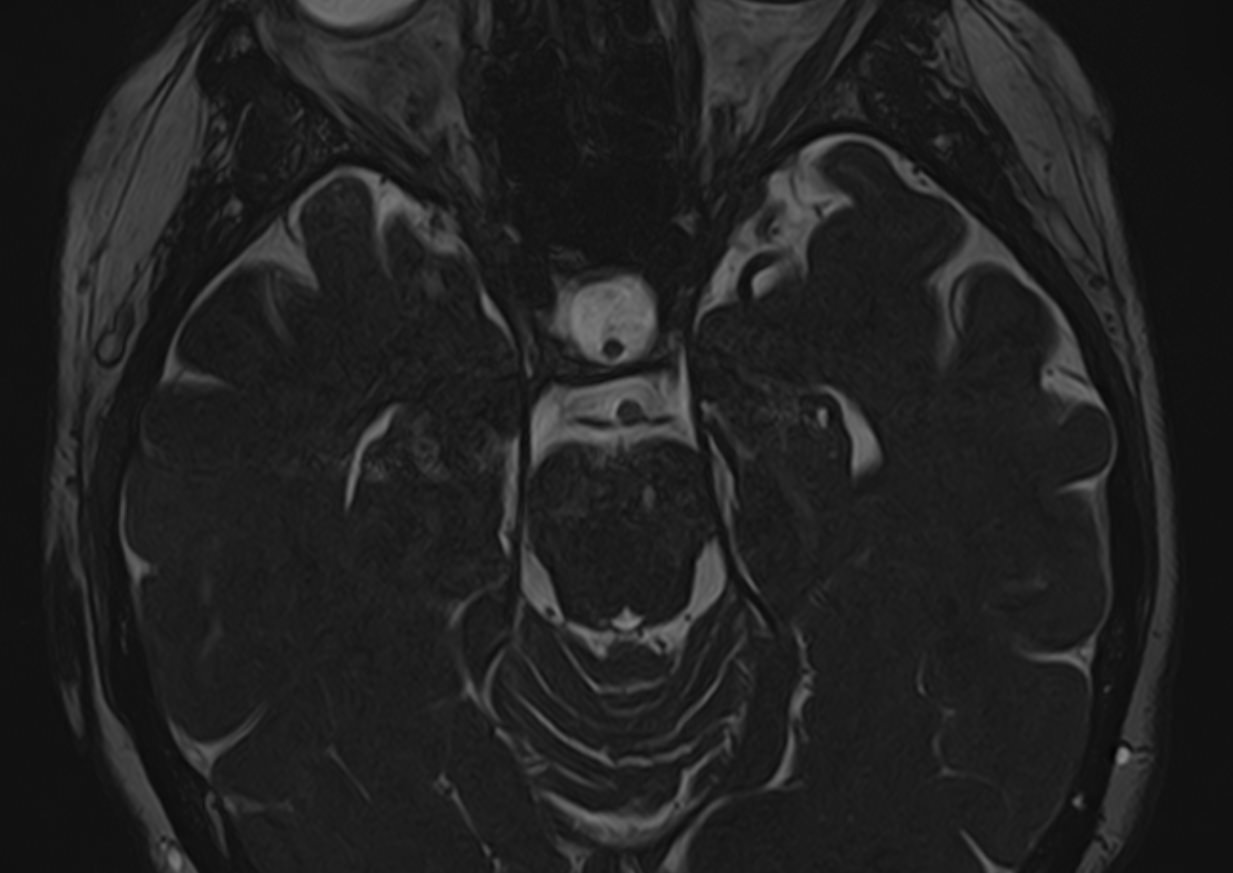

У человека в состав нервной системы входит 12 пар черепных нервов. Ядра, из которых берет начало каждый нерв, расположены в головном мозге и представляют собой скопления тел нейронов. Образованные в ядре нервные волокна выходят из черепа сквозь анатомические отверстия и далее направляются к органам чувств и мышцам. В зависимости от того, какой нерв поражен (вследствие опухоли, инфекции, травмы, воспаления, инсульта и др), происходит выпадение той или иной его функции. Это определяет разнообразие неврологической симптоматики.

Магнитно-резонансная томография позволяет детально визуализировать изменения черепных нервов и прилегающих структур. В клинике «Доступная медицина» для точной диагностики причин поражения черепно-мозговых нервов применяется новейший высокопольный 32-канальный томограф TOSHIBA VANTAGE TITAN 1,5 Тесла, который обладает высокой чувствительностью и способностью определить минимальные изменения исследуемого органа.

Признаки нарушения функций ЧМН разнообразны. Причинами поражения могут быть серьезные заболевания, которые требуют незамедлительного обращения к врачу. Для установления точного диагноза в комплексе с другими методами используют МРТ и КТ головного мозга. Оба исследования имеют свои особенности. Компьютерная томография позволяет хорошо визуализировать изменения костной ткани. На МР-изображениях лучше просматриваются мягкотканные структуры, поэтому МРТ головного мозга с прицельным осмотром черепно-мозговых нервов является методом выбора в подобных случаях.